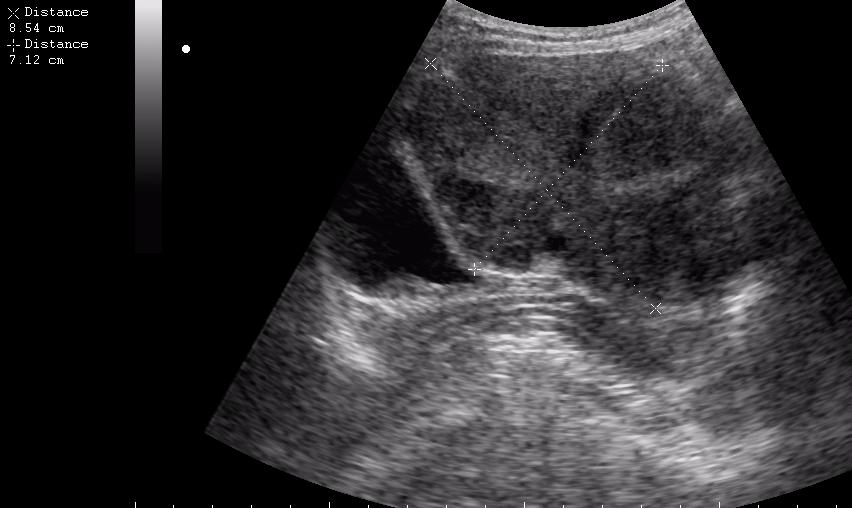

(девушке 23 года. фиброматоз матки)

ещё раз - это матка 23-летней девушки. то есть, ВСЁ это, то что Вы видите, да-да, на весь экран - это матка.

Диагноз - фиброматоз. направлена строго на север и налево. к соседям. (онкодиспансер)